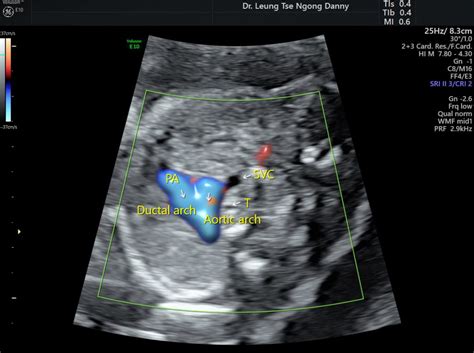

Fetal Heterotaxy And Situs Inversus | Obgyn Key

Fetal Heterotaxy and Situs Inversus | Obgyn Key obgynkey.com

fetal situs heterotaxy inversus fetus obgynkey

Fetal heterotaxy and situs inversus. Persistent left superior vena cava. Heart anatomy flow blood circulatory